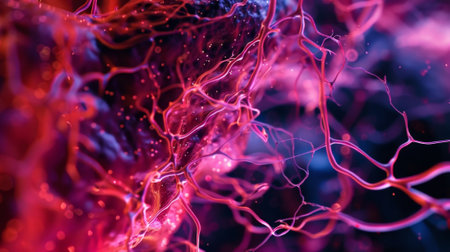

Macro view of human blood vessel network with red and blue tones showing capillaries and vein structure, ideal for illustrating medical anatomy and biology research.

Detailed visuals showcase the complex network of blood vessels in human anatomy.

Vessel flow texture in red and blue lighting showing microscopic circulation system pattern symbolizing human biology, anatomy, and healthcare science visualization.

Detailed visualization of intertwined red capillaries resembling a biological network, set against a dark blue backdrop